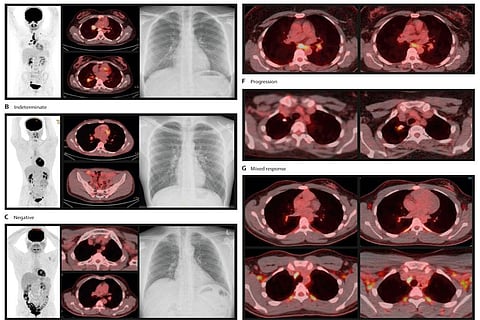

इस अध्ययन में शोधकर्ताओं ने पीईटी-सीटी इमेजिंग का उपयोग यह देखने के लिए किया कि संक्रमण कैसे बढ़ता है और रोग विकसित होने के अधिक खतरे वाले लोगों की पहचान आसानी से कैसे की जा सकती है। इस तरीके को आजमाने के लिए, लीसेस्टर एनएचएस ट्रस्ट के यूनिवर्सिटी हॉस्पिटल्स में तपेदिक रोग का इलाज करा रहे लोगों के घरों में रहने वाले 20 वयस्कों ने भाग लिया।

टीबी संक्रमण की जांच के लिए प्रतिभागियों को छाती की रेडियोग्राफी और आईजीआरए से गुजरना पड़ा। शोध टीम ने अगले वर्ष बीमारी के बढ़ने की निगरानी के लिए दो नए तरीकों का इस्तेमाल किया: पीईटी-सीटी इमेजिंग उपकरण और एक नया रक्त परीक्षण।

पीईटी-सीटी स्कैन में मरीजों को फ्लोरोडॉक्सीग्लूकोज (एफडीजी) दिया जाता है, एक रेडियोट्रेसर जो प्राकृतिक रूप से पाए जाने वाले ग्लूकोज के समान होता है। उन क्षेत्रों का विश्लेषण करके जहां रेडियोट्रेसर लिया जाता है, शरीर के उन क्षेत्रों की पहचान करना संभव है, जहां संक्रमण हो सकता है।

शोधकर्ताओं ने टीबी बैक्टीरिया द्वारा संक्रमण से जुड़ी चयापचय गतिविधि के सबूत की तलाश की, जिसे छाती के एक्स-रे का उपयोग करके नहीं देखा जा सकता है। या नियमित जांच में उपयोग किए जाने वाले रक्त परीक्षणों द्वारा नहीं देखा जा सकता है।

शोधकर्ताओं ने पाया कि रेडियोट्रेसर गतिविधि फेफड़ों के आसपास, या फेफड़ों के आसपास लिम्फ नोड्स में होती है। तीन महीने के बाद यह पता लगाने के लिए कि संक्रमण बढ़ रहा है या नहीं, दूसरा पीईटी-सीटी स्कैन किया गया। टीबी बैक्टीरिया की उपस्थिति का परीक्षण करने के लिए सक्रिय जगहों से नमूने भी लिए गए।

अध्ययन के लिए भर्ती किए गए 20 प्रतिभागियों में से एक की छाती का रेडियोग्राफ सूक्ष्म रूप से असामान्य था। पीईटी-सीटी का उपयोग करके चार लोगों की पहचान की गई, जिनमें टीबी के बैक्टीरिया को फेफड़ों के वायुमार्ग या पीईटी-पॉजिटिव लिम्फ नोड्स से अलग किया जा सकता था। दो अन्य लोगों की पहचान की गई, जिनमें दूसरे पीईटी-सीटी स्कैन के बाद भारी बदलाव हुए थे।

सभी छह लोगों को दिया गया टीबी उपचार पूरा करने के तीन महीने बाद पीईटी-सीटी स्कैन और उपचार करने के बाद बदलाव दिखाई दिए, जिससे इस विचार को बल मिला कि पीईटी-सीटी में बदलाव चयापचय रूप से सक्रिय तपेदिक संक्रमण के कारण हुए थे।